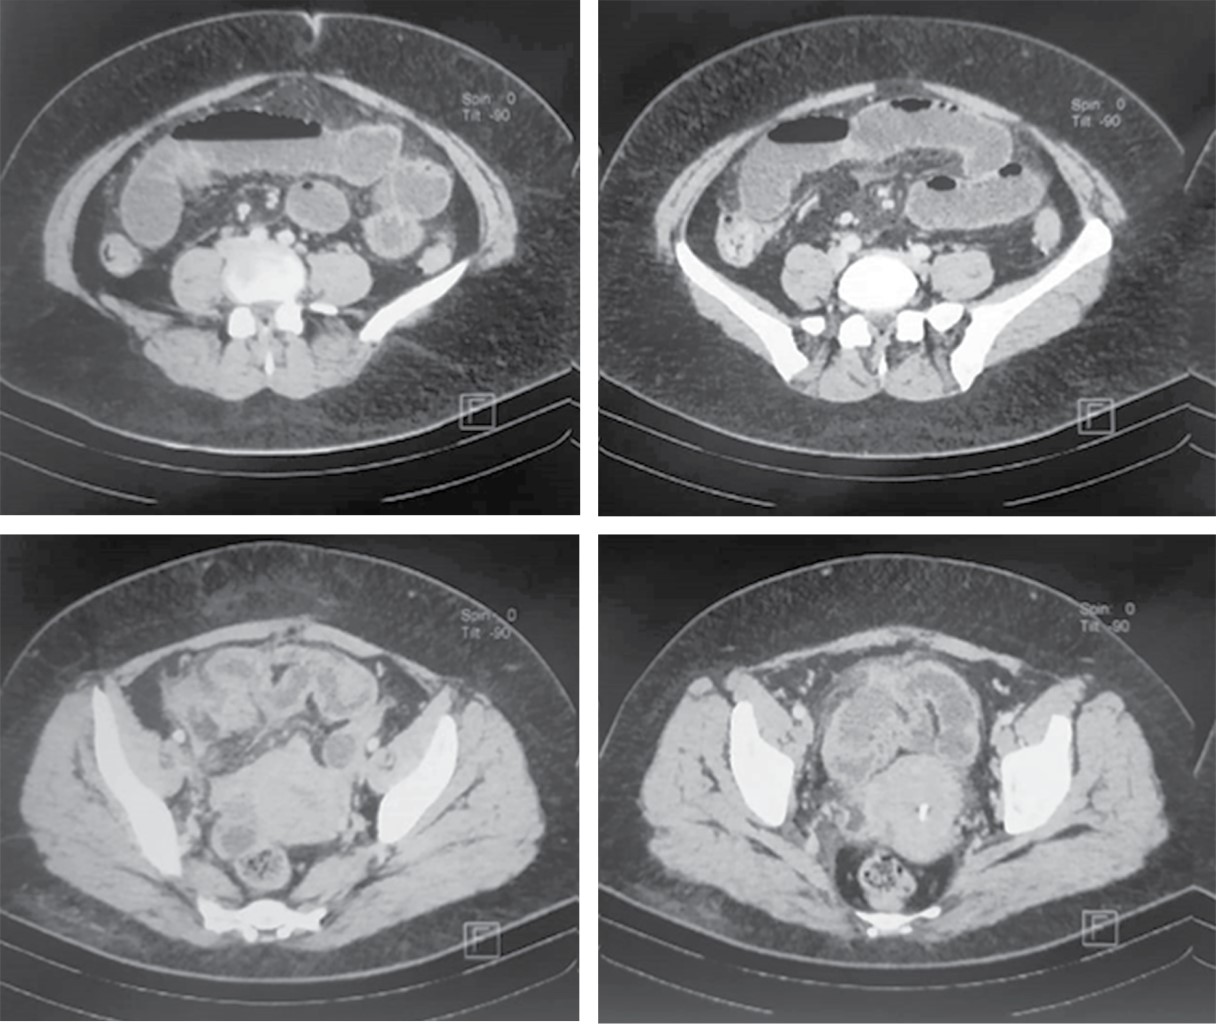

Paciente femenino de 47 años sin antecedentes no patológicos de relevancia. Tabaquismo a razón de 20 cigarros al día con índice tabáquico de 25, el cual se considera riesgo intenso para enfermedad pulmonar obstructiva crónica (EPOC); cesárea electiva hace 13 años. Inicia su padecimiento cuatro días previos a su valoración, al presentar dolor en epigastrio de intensidad 7/10 sin irradiaciones, sin desencadenantes, ni exacerbantes; acompañado de náusea y vómito en cinco ocasiones de contenido gastro-alimentario. A las 24 horas de inicio del cuadro, refiere automedicación e ingesta de butilhioscina 10 mg cada 12 horas, tras lo cual presenta leve mejoría, por lo que deja a libre evolución. A las 48 horas presenta aumento de vómitos, así como migración del dolor hacia fosa iliaca derecha, no refiere fiebre. Acude a particular a las 72 horas de inicio del cuadro, donde se administra tratamiento antibiótico con amikacina, analgésico y metoclopramida a dosis no especificadas, sin ceder el cuadro, por lo que acude a hospital particular al aumentar intensidad de dolor abdominal, en donde se le realizan estudios de laboratorio, los cuales muestran: leucocitosis de 23.3 × 10e3/μl a expensas de neutrófilos (19.48 × 10e3/μl), el resto de resultados de laboratorio sin alteraciones. Del mismo modo, al sospechar cuadro de apendicitis aguda, se solicita TC toraco-abdomino-pélvica contrastada, la cual se reporta con probable apendicitis aguda complicada con absceso localizado, así como hallazgos de broncograma aéreo y datos sugestivos de neumonía atípica por SARS-CoV-2, CO-RADS 4 (Figuras 1 y 2), por lo que deciden envío a urgencias de nuestra unidad.

Figura 2